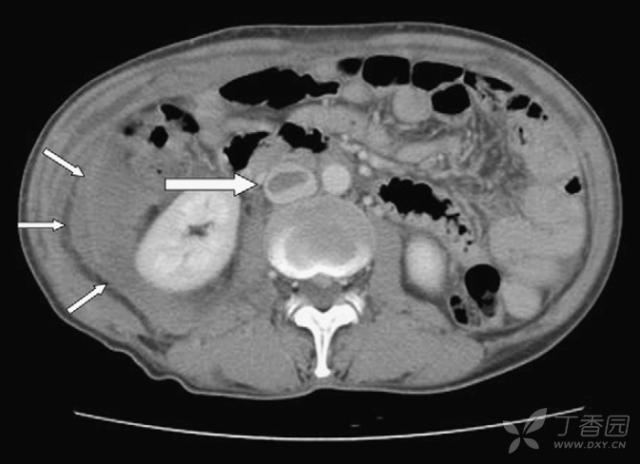

入院第二日早晨,全腹CT增强扫描提示:腹腔积液,盆腔血肿(箭头所指:10*5.7cm,较入院时增加);

右侧腹膜后巨大血肿达右肾周围,肾门水平处下腔静脉及右侧髂总、髂内外静脉内见血栓。

粗箭头所指:下腔静脉扩张伴血栓形成;细箭头所指:盆腔血肿增大至右肾水平